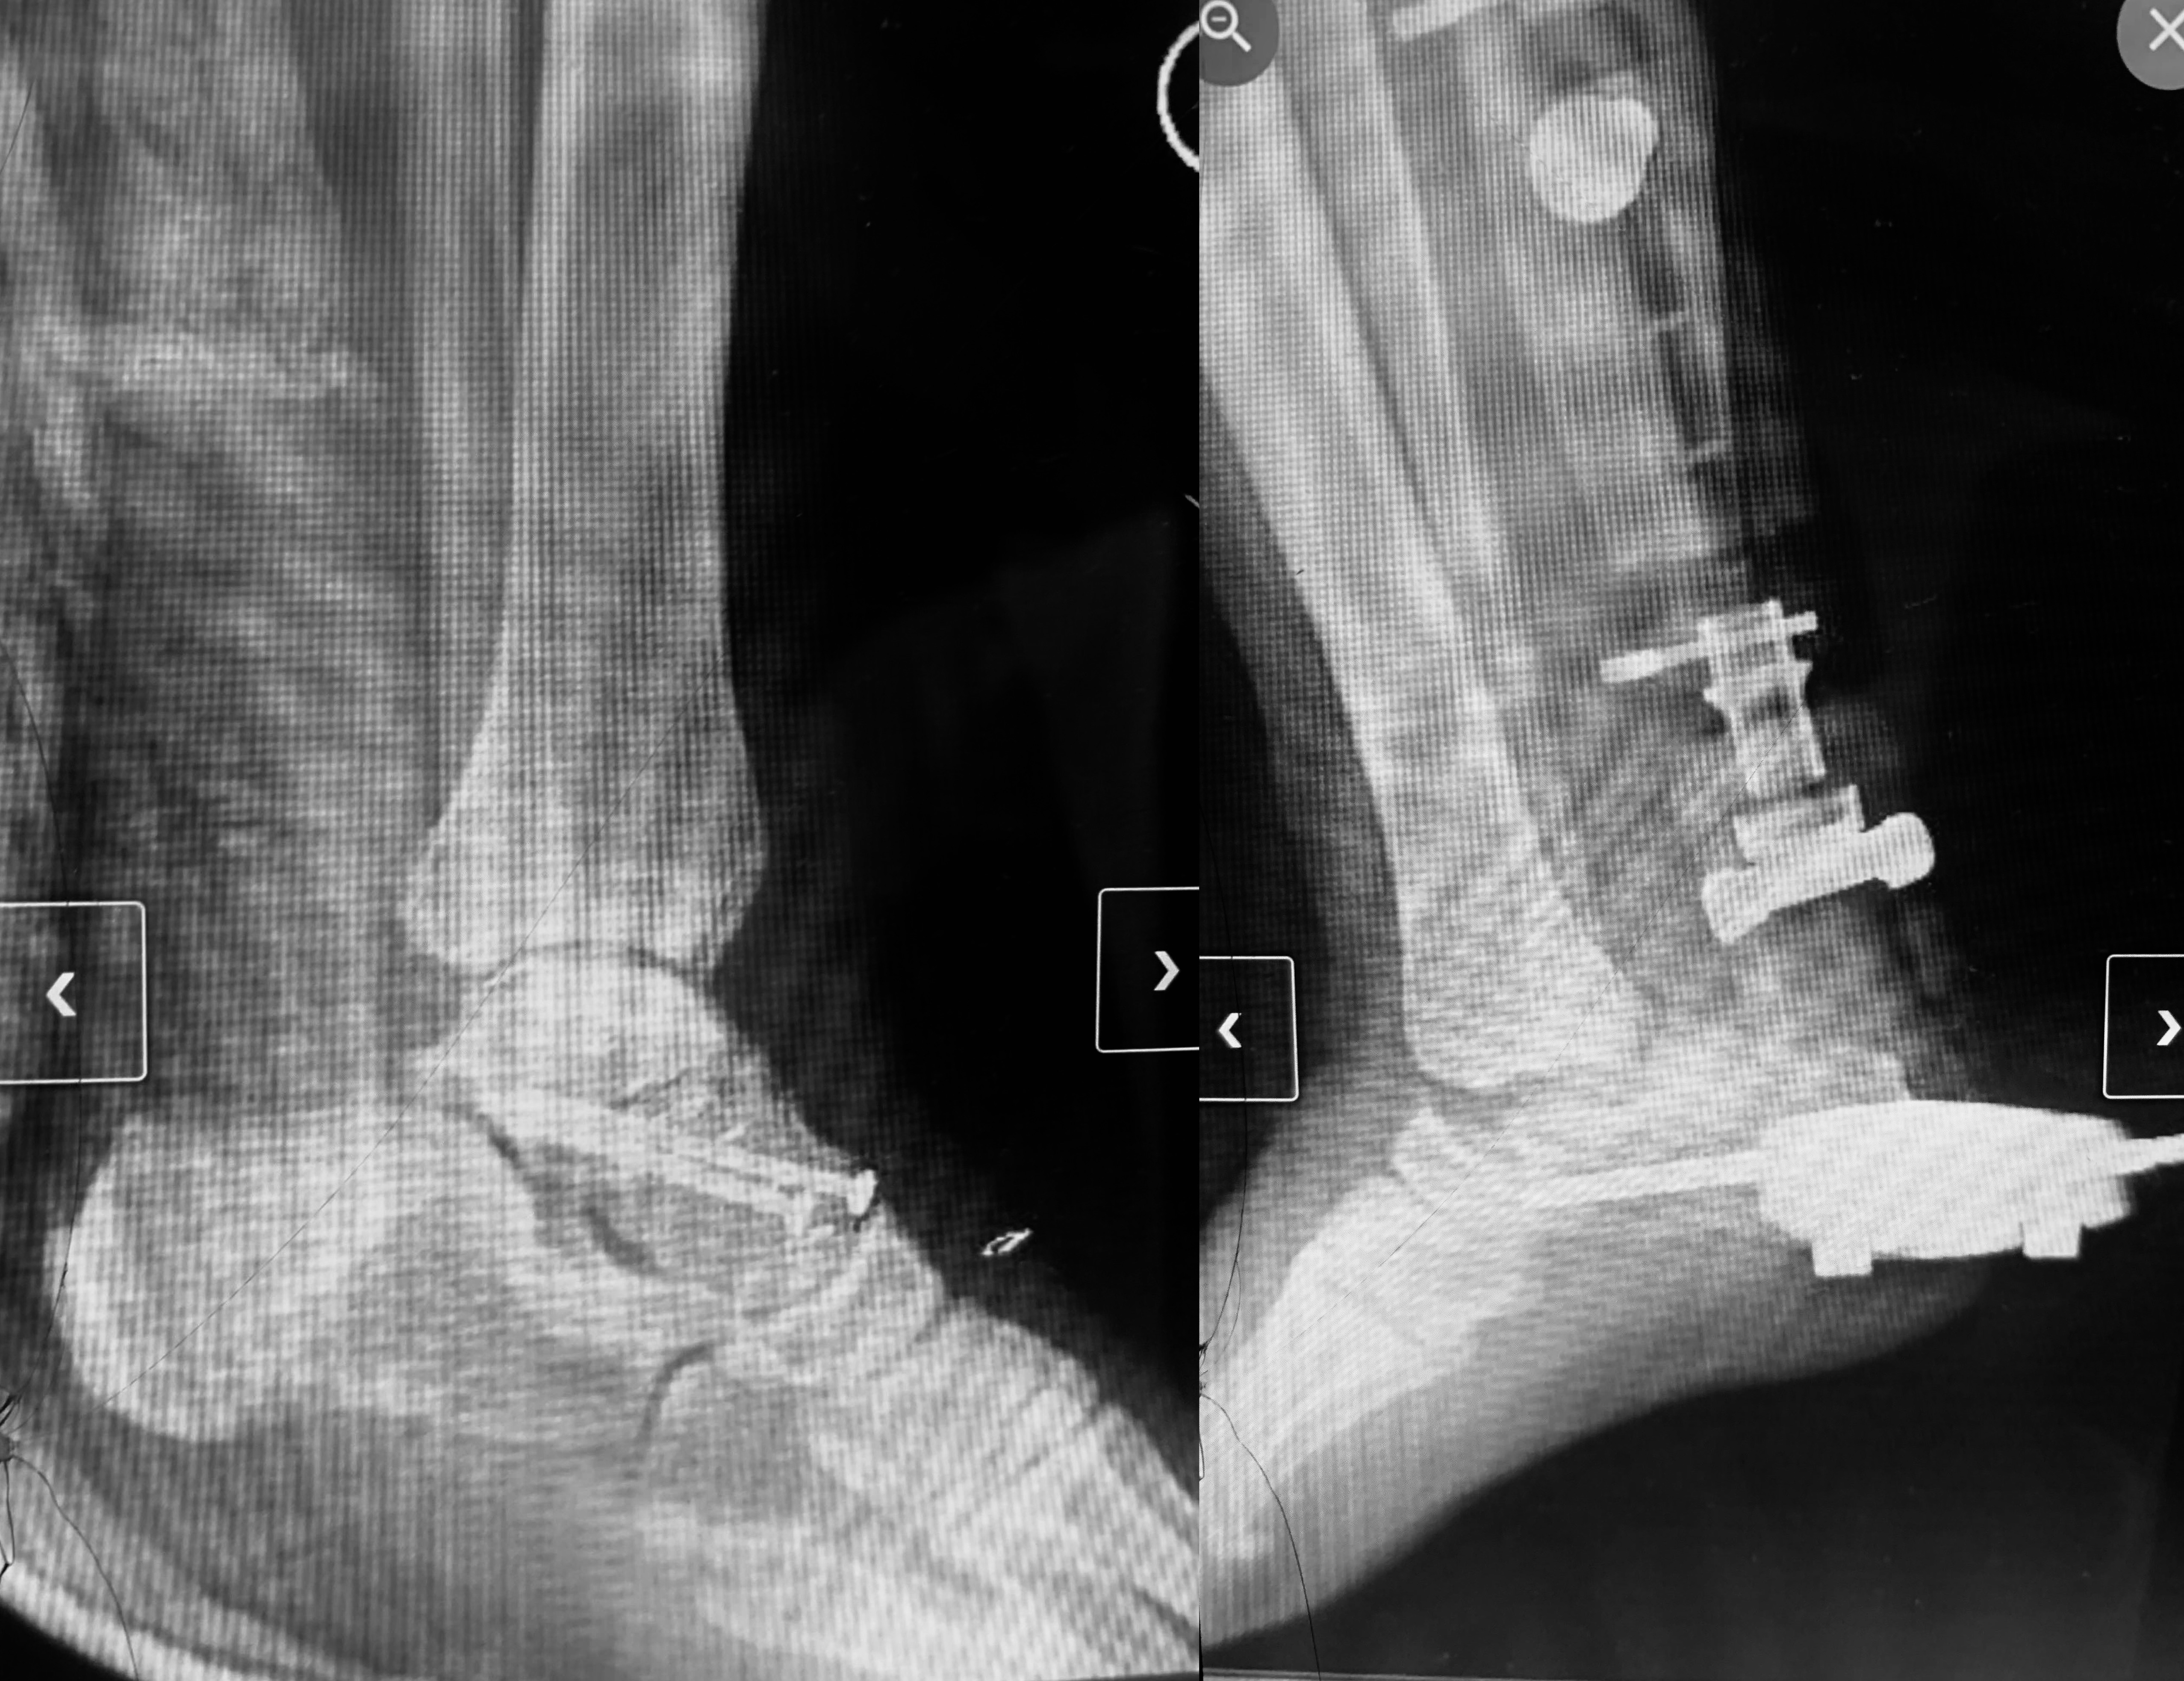

His left foot is broken and now held together with screws. His right foot suffered catastrophic damage; his talus bone popped out of his ankle, and his foot was nearly severed, held on only by tendons and skin. At the scene, I applied two tourniquets and elevated his leg to stop the bleeding by his instruction that he was able to give calmly despite the pain until paramedics arrived. When they eventually arrived, one of the paramedics foolishly stepped on his left foot, causing him immense pain. Even after yelling at him over and over, he just kept stepping on him.